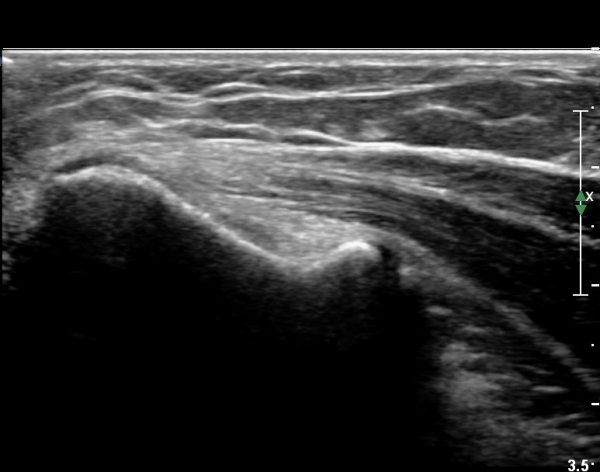

ÃÊÀ½ÆÄ °Ë»ç

³»»ó°ú Á¾´Ü¸é°Ë»ç¿¡¼­ ³»»ó°ú ±¼°ñ°Ç ºÎÂøºÎ¿¡ Àú¿¡ÄÚ º´º¯ÀÌ °üÂûµÈ´Ù. °Ç ½ÉºÎÀÇ

³»ÃøºÎÀδë´Â ƯÀÌ ¼Ò°ßÀ» º¸ÀÌÁö ¾Ê´Â´Ù(±×¸² 1, 2).

ŽÃËÀÚ¸¦ Á¶±Ý À̵¿ÇÏ´Ï °Ç ÀϺδ Á¤»óÀûÀÎ ¼Ò°ßÀ» º¸À̰í ÀÖ´Ù(±×¸² 3).